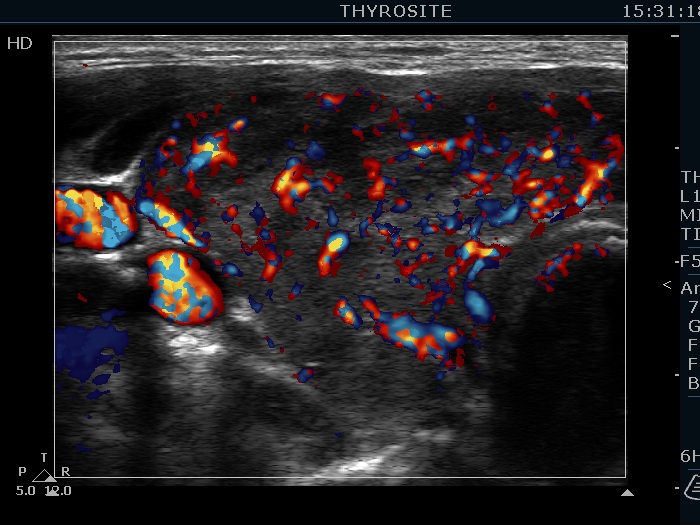

Consecutively operated patients with autoimmune thyroid disease - case 17 (1573) (ultrasonographic picture 3)

Right lobe, transverse view, color Doppler mode. The vascularization is significantly increased.